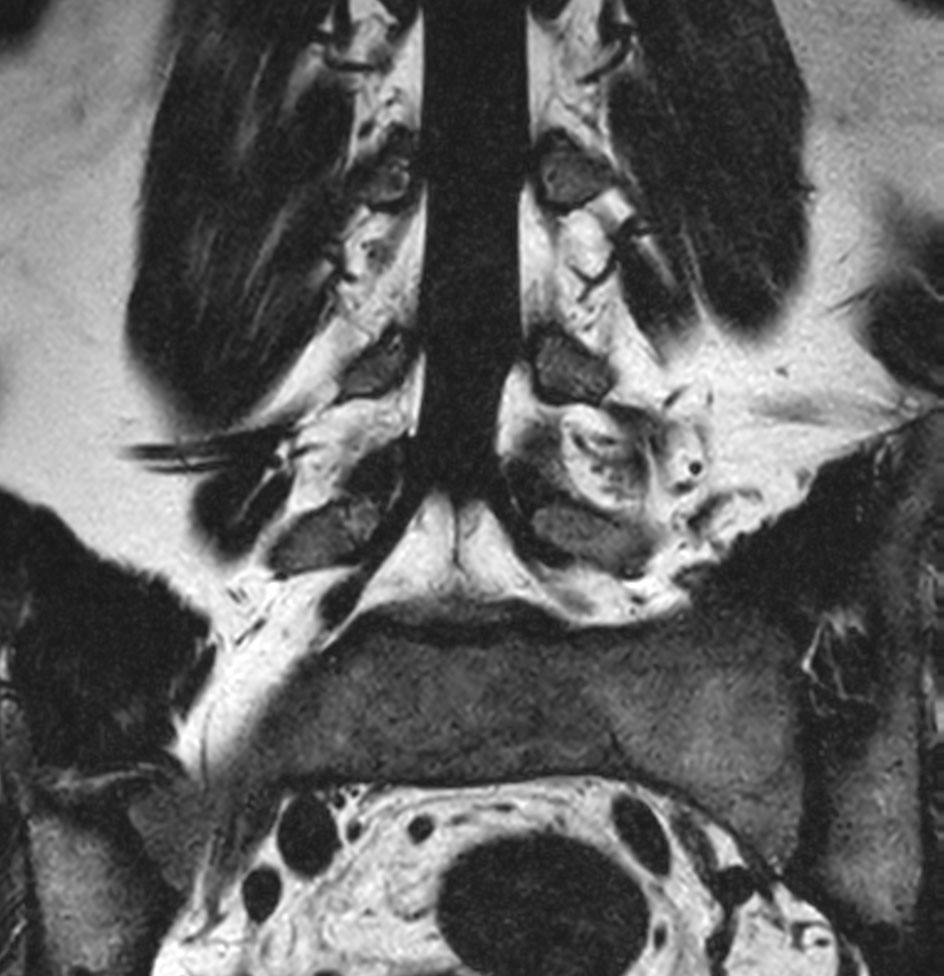

Patient with a lumbar spine bulging disc.

Coronal T2w mDIXON XD TSE (Water only)